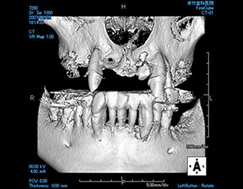

しかしながら、立体的な被写体(歯、顎骨など)に対してフィルムやパソコン上に写っているものはあくまで平面的な(2次元的な)像で実物とは異なります。

私たち歯科医師は知識と経験から頭の中で得られた画像を立体的にふくらませているというのが一般的なのです。

そこには像のゆがみや、実際の治療の段階で想定外の口腔内の状態であることが多くあるのも事実です。

CT 撮影をすることによってインプラントを埋入する骨の状態(厚み、高さ、欠損状態、密度)や神経・血管の位置をあらかじめ正確に把握でき、安全に速いインプラント治療が可能となりました。